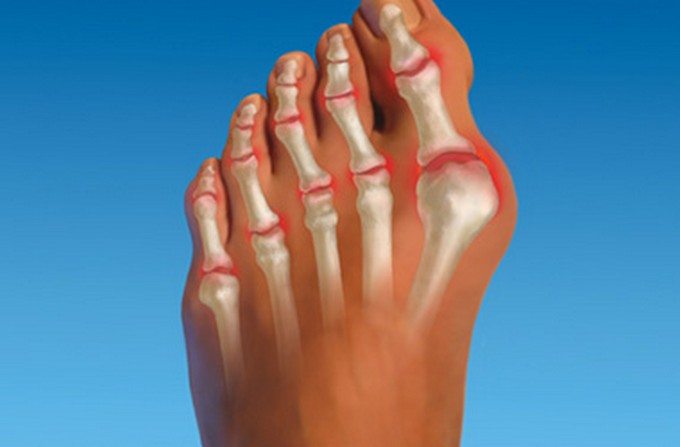

Наиболее часто воспалительный процесс протекает в суставах предплюсны, плюсны. Он нередко сочетается с артритом голеностопа или пальцев стопы.

Подвижность стопы ограничивается, уменьшается объем, амплитуда движений. К этому приводит формирование остеофитов (костных наростов). Человек и сам намеренно избегает делать полноценный упор на стопу, чтобы не спровоцировать появления болей. Это становится причиной изменения походки.

- отек мягких тканей, сдавливающий чувствительные нервные окончания, усиливающий выраженность болезненности;

- разглаживание, покраснение кожи над пораженными суставами, повышение местной температуры.